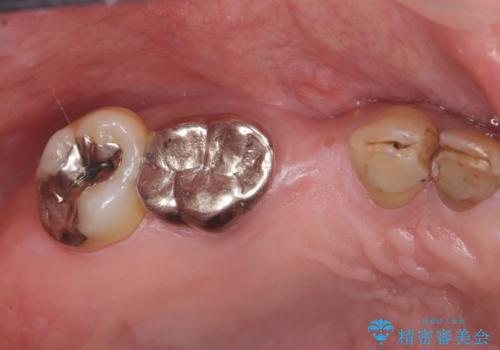

- 銀歯だらけの口腔内で将来歯がなくなるのではないかと不安になり、精査、治療を求めて来院されました。

歯周病や虫歯・強度の問題がありながらも無理やり残していた長期的な予後の見込めない歯を抜去し、インプラントを用いてしっかりと噛めるような口腔内環境の確立を目指します。